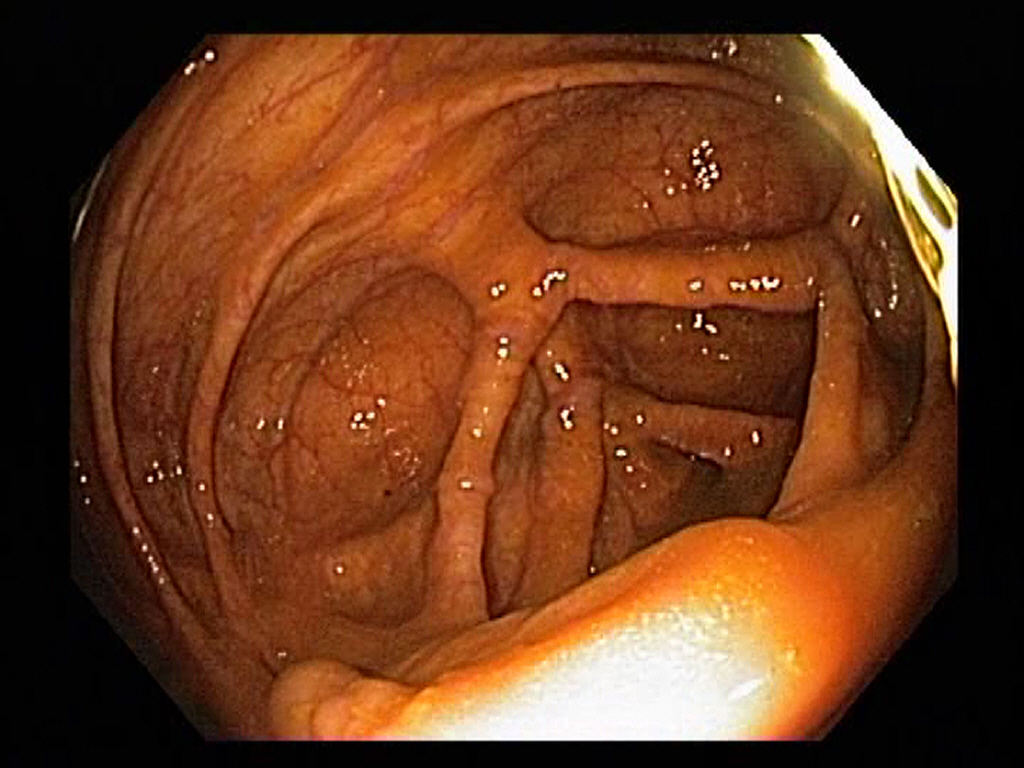

Normal Ascending Colon